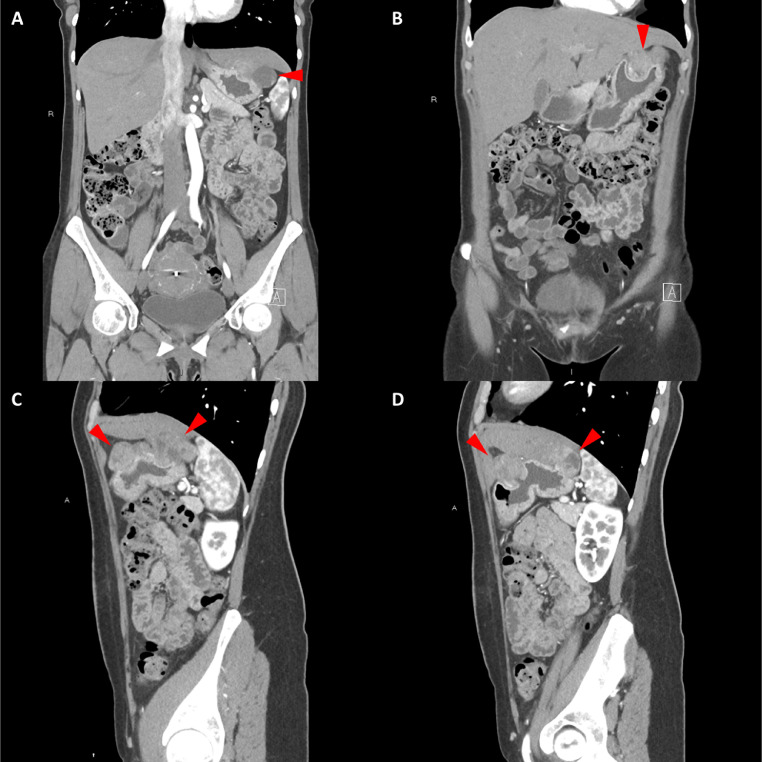

頸部增強(qiáng) CT 顯示 2 個(gè)強(qiáng)烈強(qiáng)化的腫塊。 一個(gè)位于頸部右側(cè),位于右側(cè)頸內(nèi)動(dòng)脈后方的頸動(dòng)脈間隙中,位于莖突內(nèi)側(cè),大小為 24 × 24 × 30 mm,頸靜脈橫向移位(圖 1A)。 第二個(gè)位于左側(cè)頸動(dòng)脈間隙,在分叉處正上方展開頸外動(dòng)脈和頸內(nèi)動(dòng)脈,尺寸為 15 × 18 × 22 mm(圖 1B)。 影像學(xué)檢查結(jié)果與右側(cè)迷走神經(jīng)和左側(cè)頸動(dòng)脈體副神經(jīng)節(jié)瘤一致,與之前的活檢結(jié)果一致。

Fig. 1

圖1:右側(cè)迷走神經(jīng)和左側(cè)頸動(dòng)脈體副神經(jīng)節(jié)瘤。 (A) 軸位增強(qiáng) CT 顯示右側(cè)頸動(dòng)脈間隙、右側(cè)頸內(nèi)動(dòng)脈后方(白色箭頭)和莖突內(nèi)側(cè)有強(qiáng)烈強(qiáng)化的腫塊(紅色箭頭)。 (B) 軸位對(duì)比增強(qiáng) CT 顯示左頸動(dòng)脈間隙有強(qiáng)烈強(qiáng)化的腫塊(紅色箭頭),向后張開頸內(nèi)動(dòng)脈(紅色箭頭),向前張開頸外動(dòng)脈(紅色箭頭)。 (C) 冠狀對(duì)比增強(qiáng) CT 顯示兩個(gè)增強(qiáng)腫塊(紅色箭頭)。